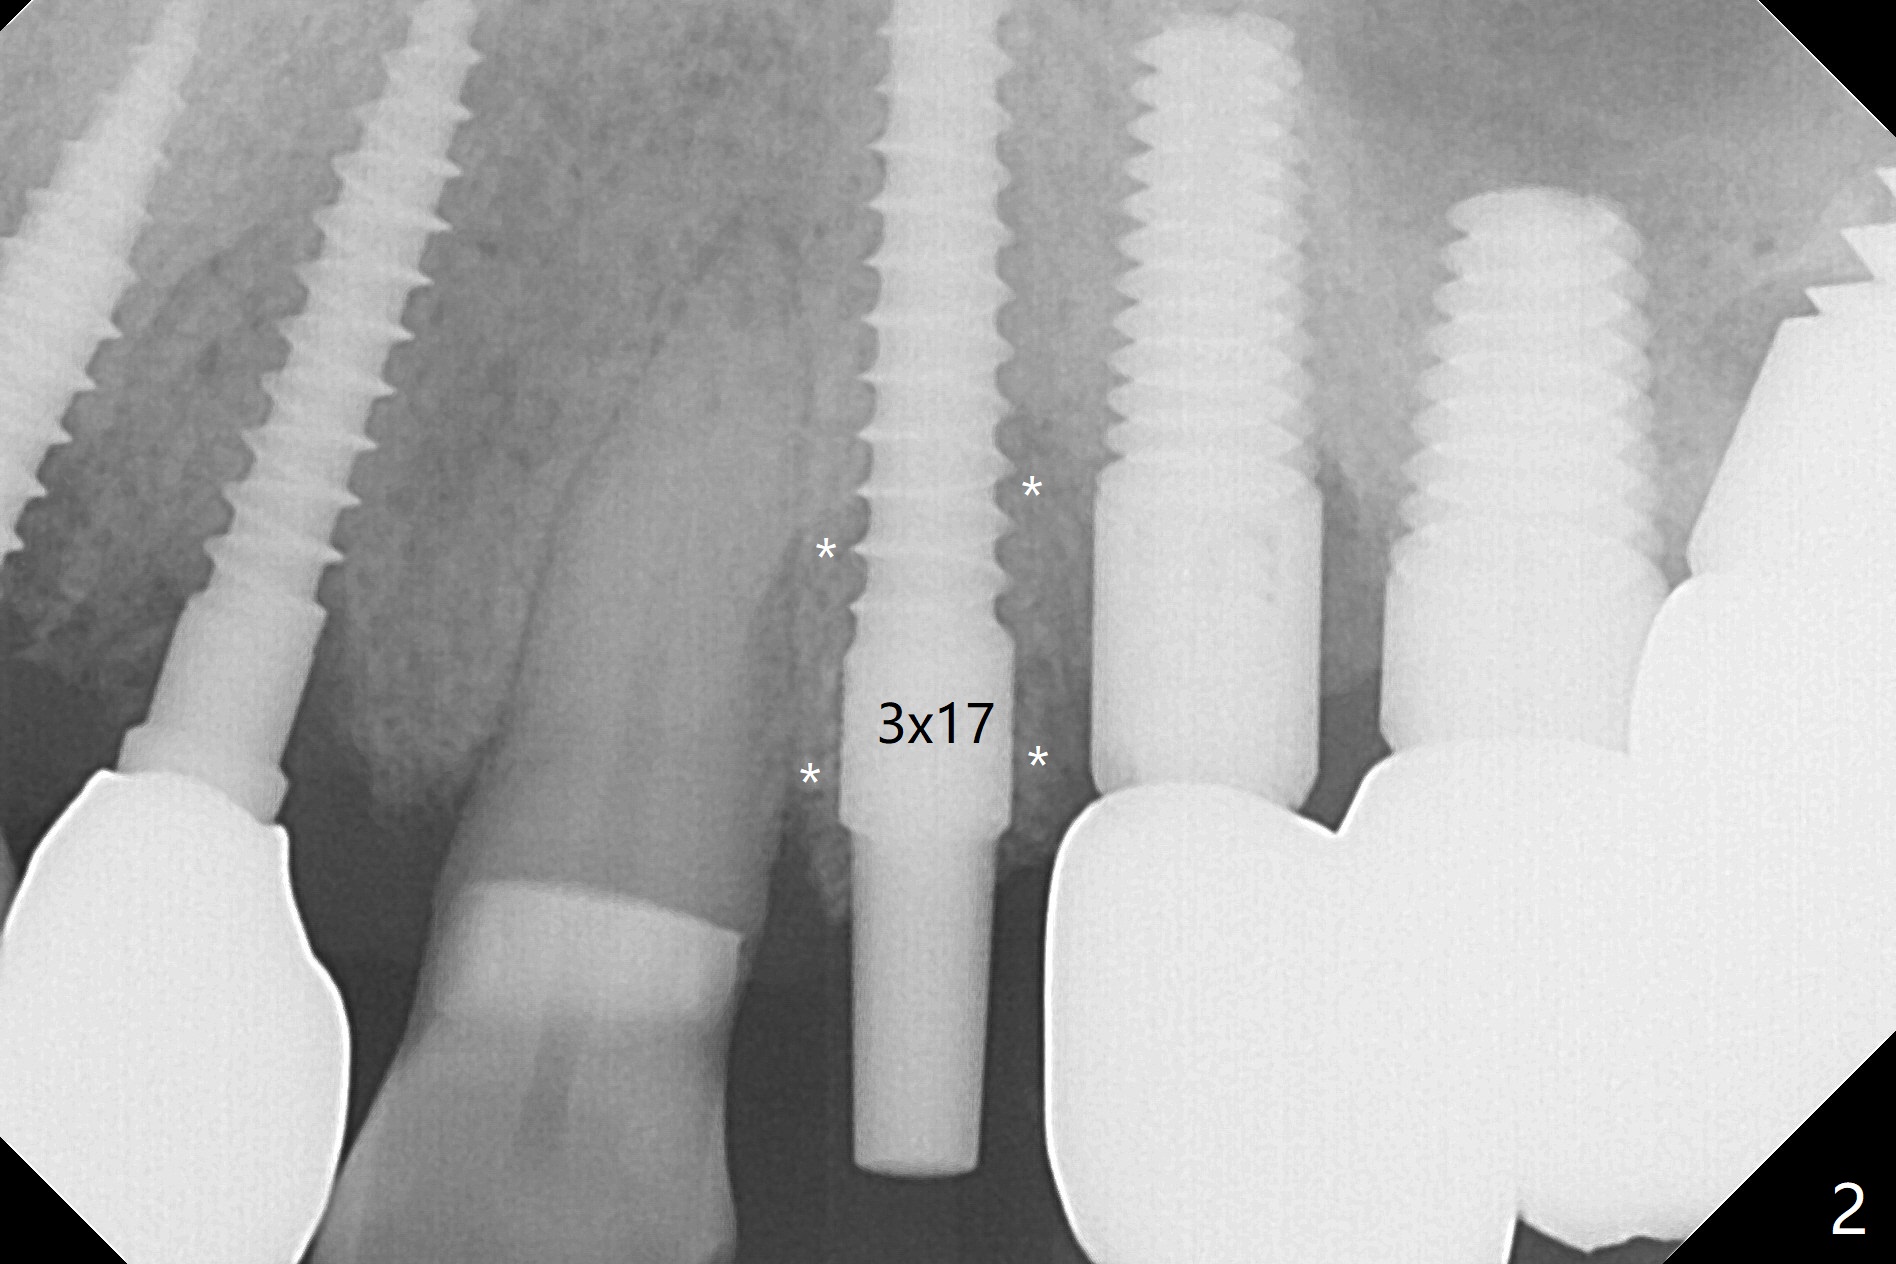

66岁男士口腔卫生好,但是许多牙齿可能因为咀嚼力太大,骨质吸收而失去,包括左上四(没有颊侧骨板),拔除后2毫米钻头显示钻洞接近尖牙(图一),好像不容易改变钻洞位置,病人对手术恐惧,干脆植入一段式植体(图二,三)。植骨后(图二*),制备即刻临时牙冠。后者戴入前不小心颊侧边缘过度修正,就在原位添加树脂,两周后显得胖些(图四 *),远中形成倒凹,不容易取出,只好稍微修正。